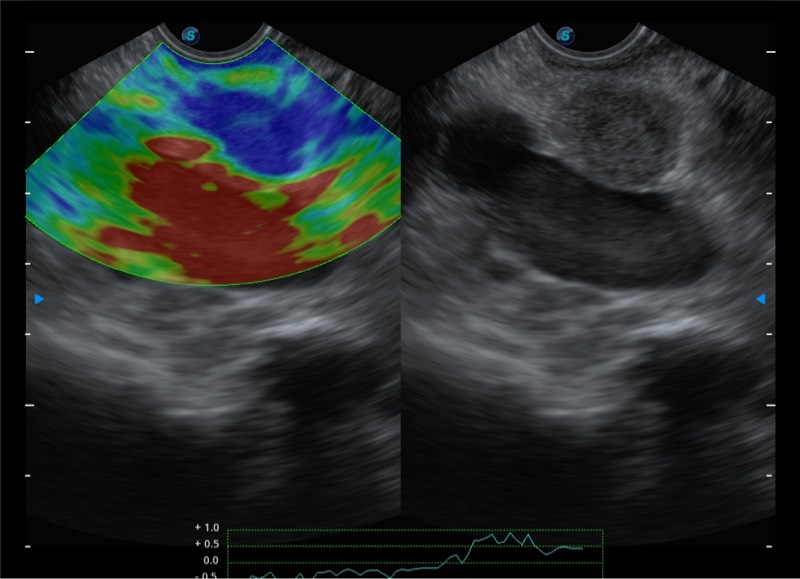

高端超声影像平台

基于二十年的超声技术积累,DB中国旗舰官方网站提供了最新一代的独立超声主机,在提供高质量图像的同时满足多学科使用。具备常见多普勒技术并提供弹性成像、声学造影等高端影像技术。新一代传感器具有更强的抗干扰能力并减少图像伪影。